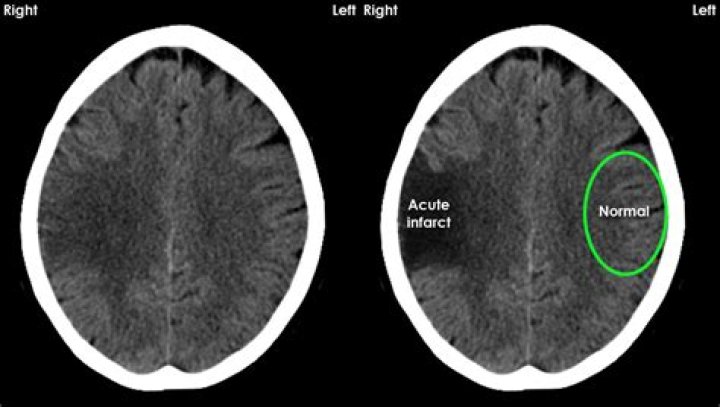

Each radiologist classified patients into two groups: “no acute findings” and “acute findings”. An acute finding was defined as any CT abnormality explaining the symptoms and related to emergency findings. Incidental findings considered as not related to the patient's symptoms were not included in acute findings.